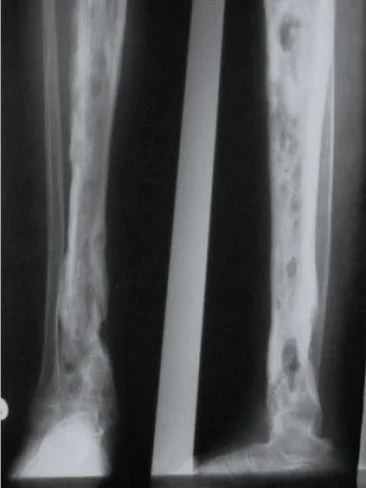

(C) Bony sequestrum X-ray leg (left; AP view) of a child A fragment of bone has separated from adjacent bone and is surrounded by a lucent rim. chronic osteomyelitis.Â

Radiology

Findings:

- X-ray: Rarefaction surrounded by sclerosis

- Cavities and sequestra (bacteria adheres to dead bone and escapes the antibiotic effect)

- Sclerosis. Bone destruction, cavities, new bone formation, sequestrum